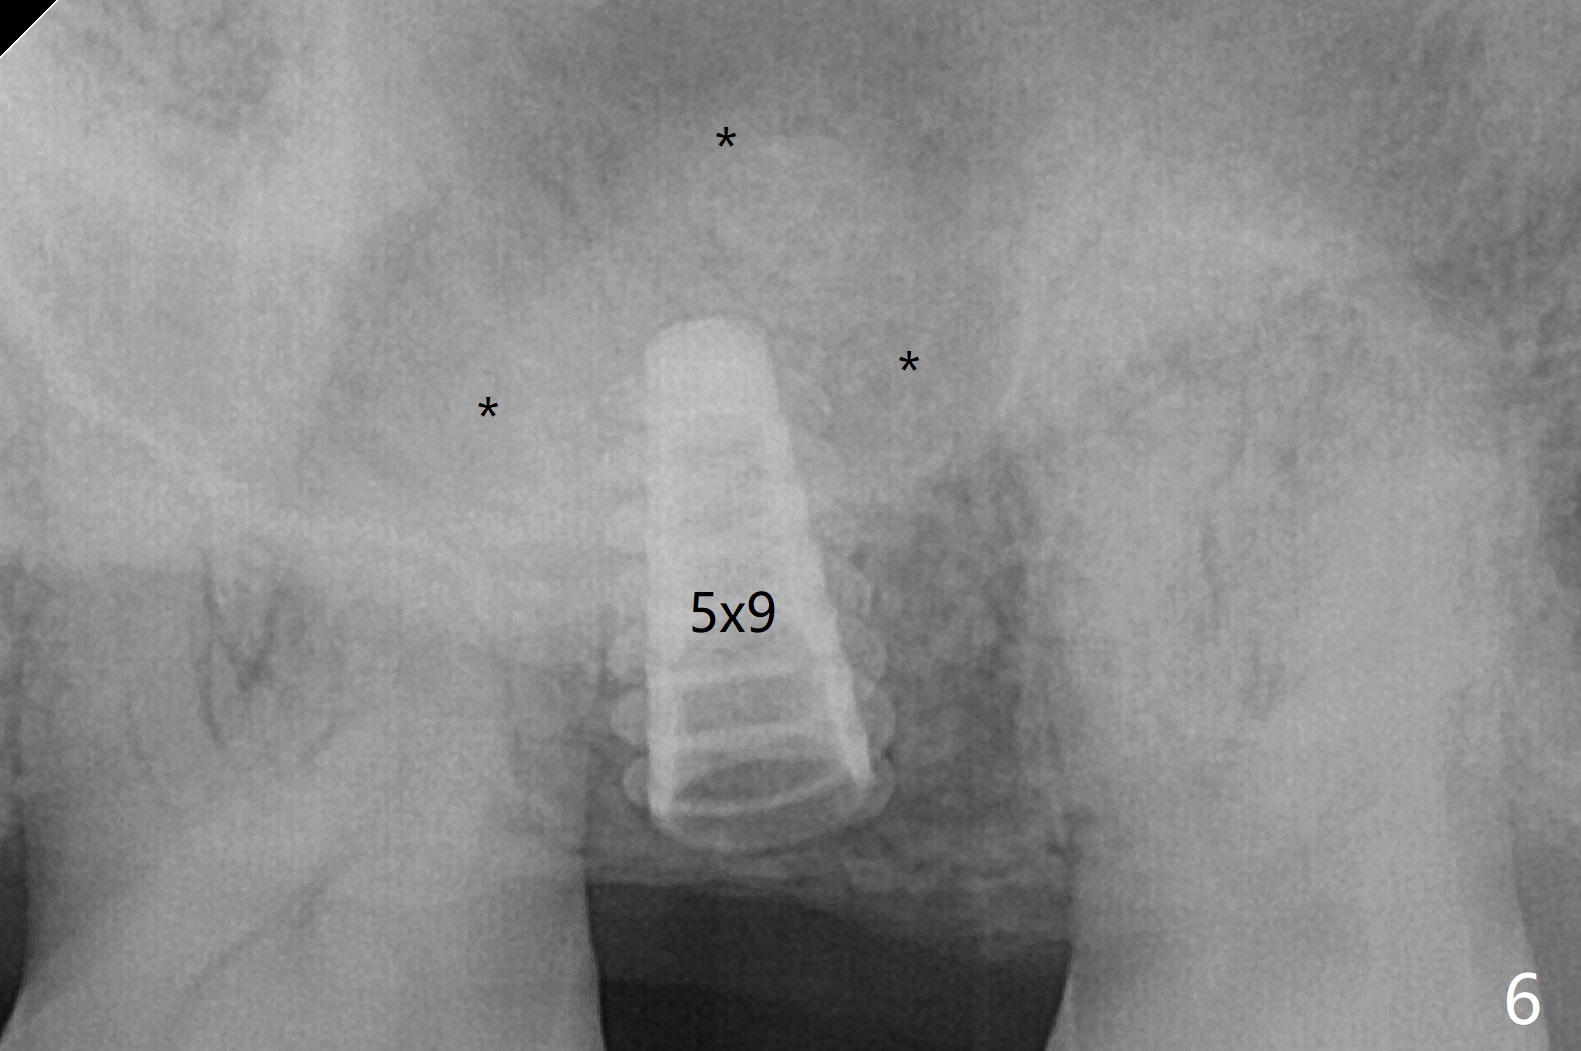

2号牙位点保存后6个月,而15号牙拔除没有植骨1-2年前(图一)。2号牙位骨质高度足够,准备不做上颌窦提升(图二),而15号牙位需要提升(图三,六)。种植术后5个月两个植体愈合均正常(图十一,十二)。